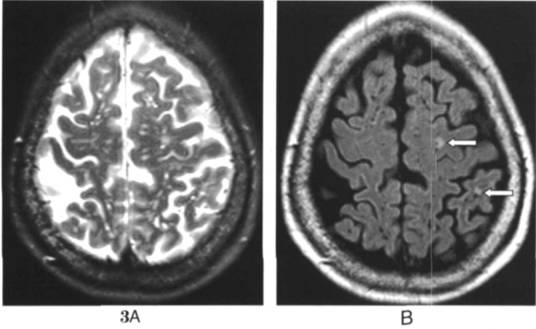

横断位T2WI显示双侧半卵圆中心多发斑点状高信号灶;B.同一层面FLAIR显示为斑点状低信号,周围脑实质信号正常。左侧半球两个病灶(箭示)显示为中央低信号,周围高信号,此为陈旧性腔隙性脑梗塞